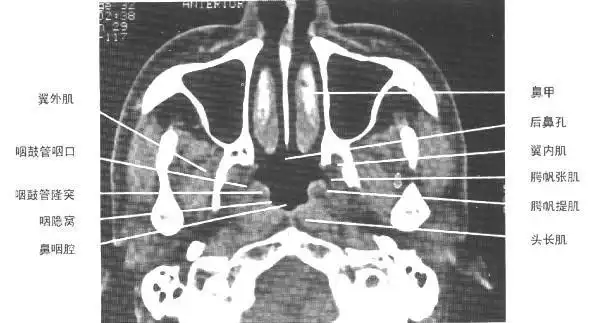

鼻部ct会诊

正常鼻咽鼻窦ct影像-医学影像图